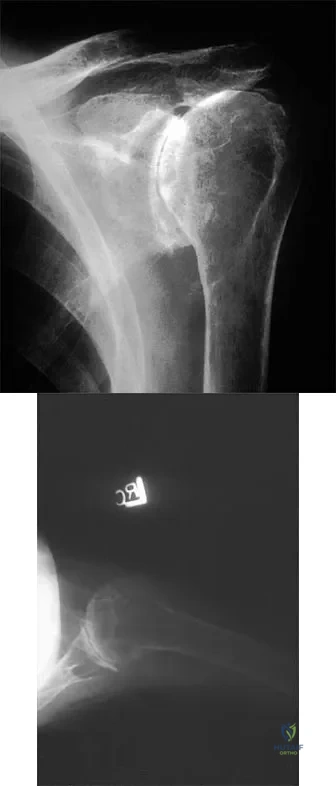

A 32-year-old man has posttraumatic arthritis after undergoing open reduction and internal fixation of a left acetabular fracture. A total hip arthroplasty is performed, and the radiograph is shown in Figure 18. What is the most common mode of failure leading to revision in this group of patients?

Explanation

Figure 44 shows the AP radiograph of the hip of a patient who underwent screw fixation of the acetabulum. Which of the following structures is at least risk for injury during screw placement in the acetabular component?

Explanation